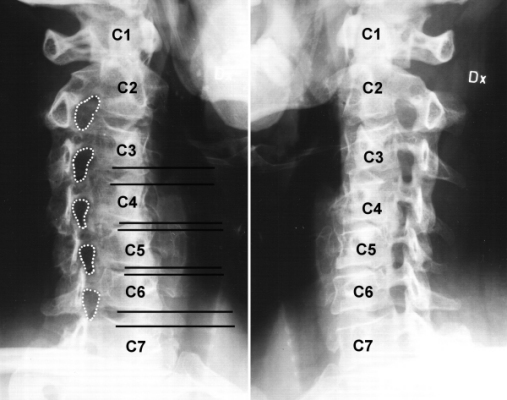

Bild 1.1. Visar var värken började.

Bild 1.2. Resultat av s.k. slätröntgen 20011205.

Bild 1.2.a "Kotförskjutning" som påverkar "hålet" (foramen intervertebralis)

A & B i bilden visar hur stora "hålen" skulle ha varit om diskarna varit "vanliga". Jag har alltså "dragit" isär kotorna och "återställt" mellanrummen C4-C5 & C5-C6. Vid C & D har jag med mörkgrått markerat den "yta" som p.g.a. "kotförskjutningen försvinner". Här visas mitt nuvarande "mellanrum".

I bild 1.2 har markerat respektive kota i halsryggen med motsvarande anatomisk beteckning. C1-C7. "C" betyder här "cervical". De svarta heldragna horisontella linjerna visar mellanrummen mellan kotorna. Mellanrummen ska normalt vara ungefär lika stora. Här ser ni att mellanrummen C3-C4 & C6-C7 är bredare än mellanrummen mellan C4-C5 & C5-C6. Röntgenläkarna beskriver detta som "måttlig disksänkning". Och det är inget bevis, i sig självt, på att man har diskbråck. Med åldern sker normalt en s.k. degenerering. Diskarna "vittrar" ned, krymper, blir mindre. Men då borde inte skillnaderna vara så stora, eller?

Jag har också prickat med vita prickar nästan ovala hål, utmed ryggraden (bild 1.2). I dessa "hål" löper ryggradsnerverna ut. Jämför hålen mellan C2-C3, C3-C4 & C6-C7 med hålen mellan C4-C5 & C5-C6. De sistnämnda hålen är något mindre (lägre och smalare) än de ovanför och det nedanför. Normalt ska de vara ungefär lika stora. Givetvis är hålen mindre på höjden eftersom avståndet mellan de kotor som har "disksänkning" är mindre. Men de är också smalare. Det borde de inte vara så. Till viss del blir de smalare p.g.a. att de "leder" som kotorna har är "snedställda" på så sätt att när eller om man får en disksänkning så gör denna "snedställda" led att kotorna "förskjuts" lite framåt/bakåt. (Se bild 1.2.a). Ytterligare en anledning till att det ser ut så här på mig, beror på att jag också har något man kan kalla för "benpålagringar" i dessa områden. Med ett "finare" ord kallas det "stenos".

Rent objektivt innebär detta att de nerver som löper ut från ryggmärgen, nerverna C6 och C5 (håll med om att det är lite förvirrande att de har samma beteckning som kotorna), får mindre utrymme än de ovanför och nedanför.